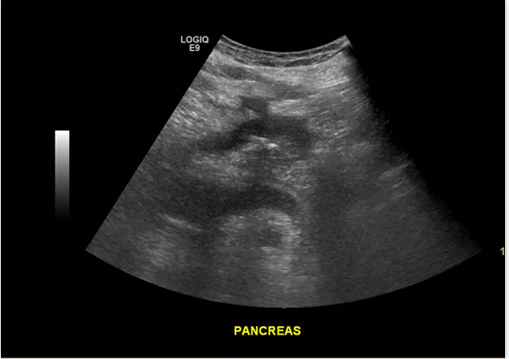

Páncreas hipoecogénico, heterogéneo, de bordes irregulares.

Líquido libre adyacente (Edema)

Hallazgo sugerente: Pancreatitis Aguda

Páncreas heterogéneo con líquido libre peripancreático

Signos de Pancreatitis Aguda.

• Difusa: Aumento de tamaño del Páncreas, disminución de ecogenicidad respecto a parénquima hepático, eco estructura heterogénea. Extra pancreático: Líquido, edema